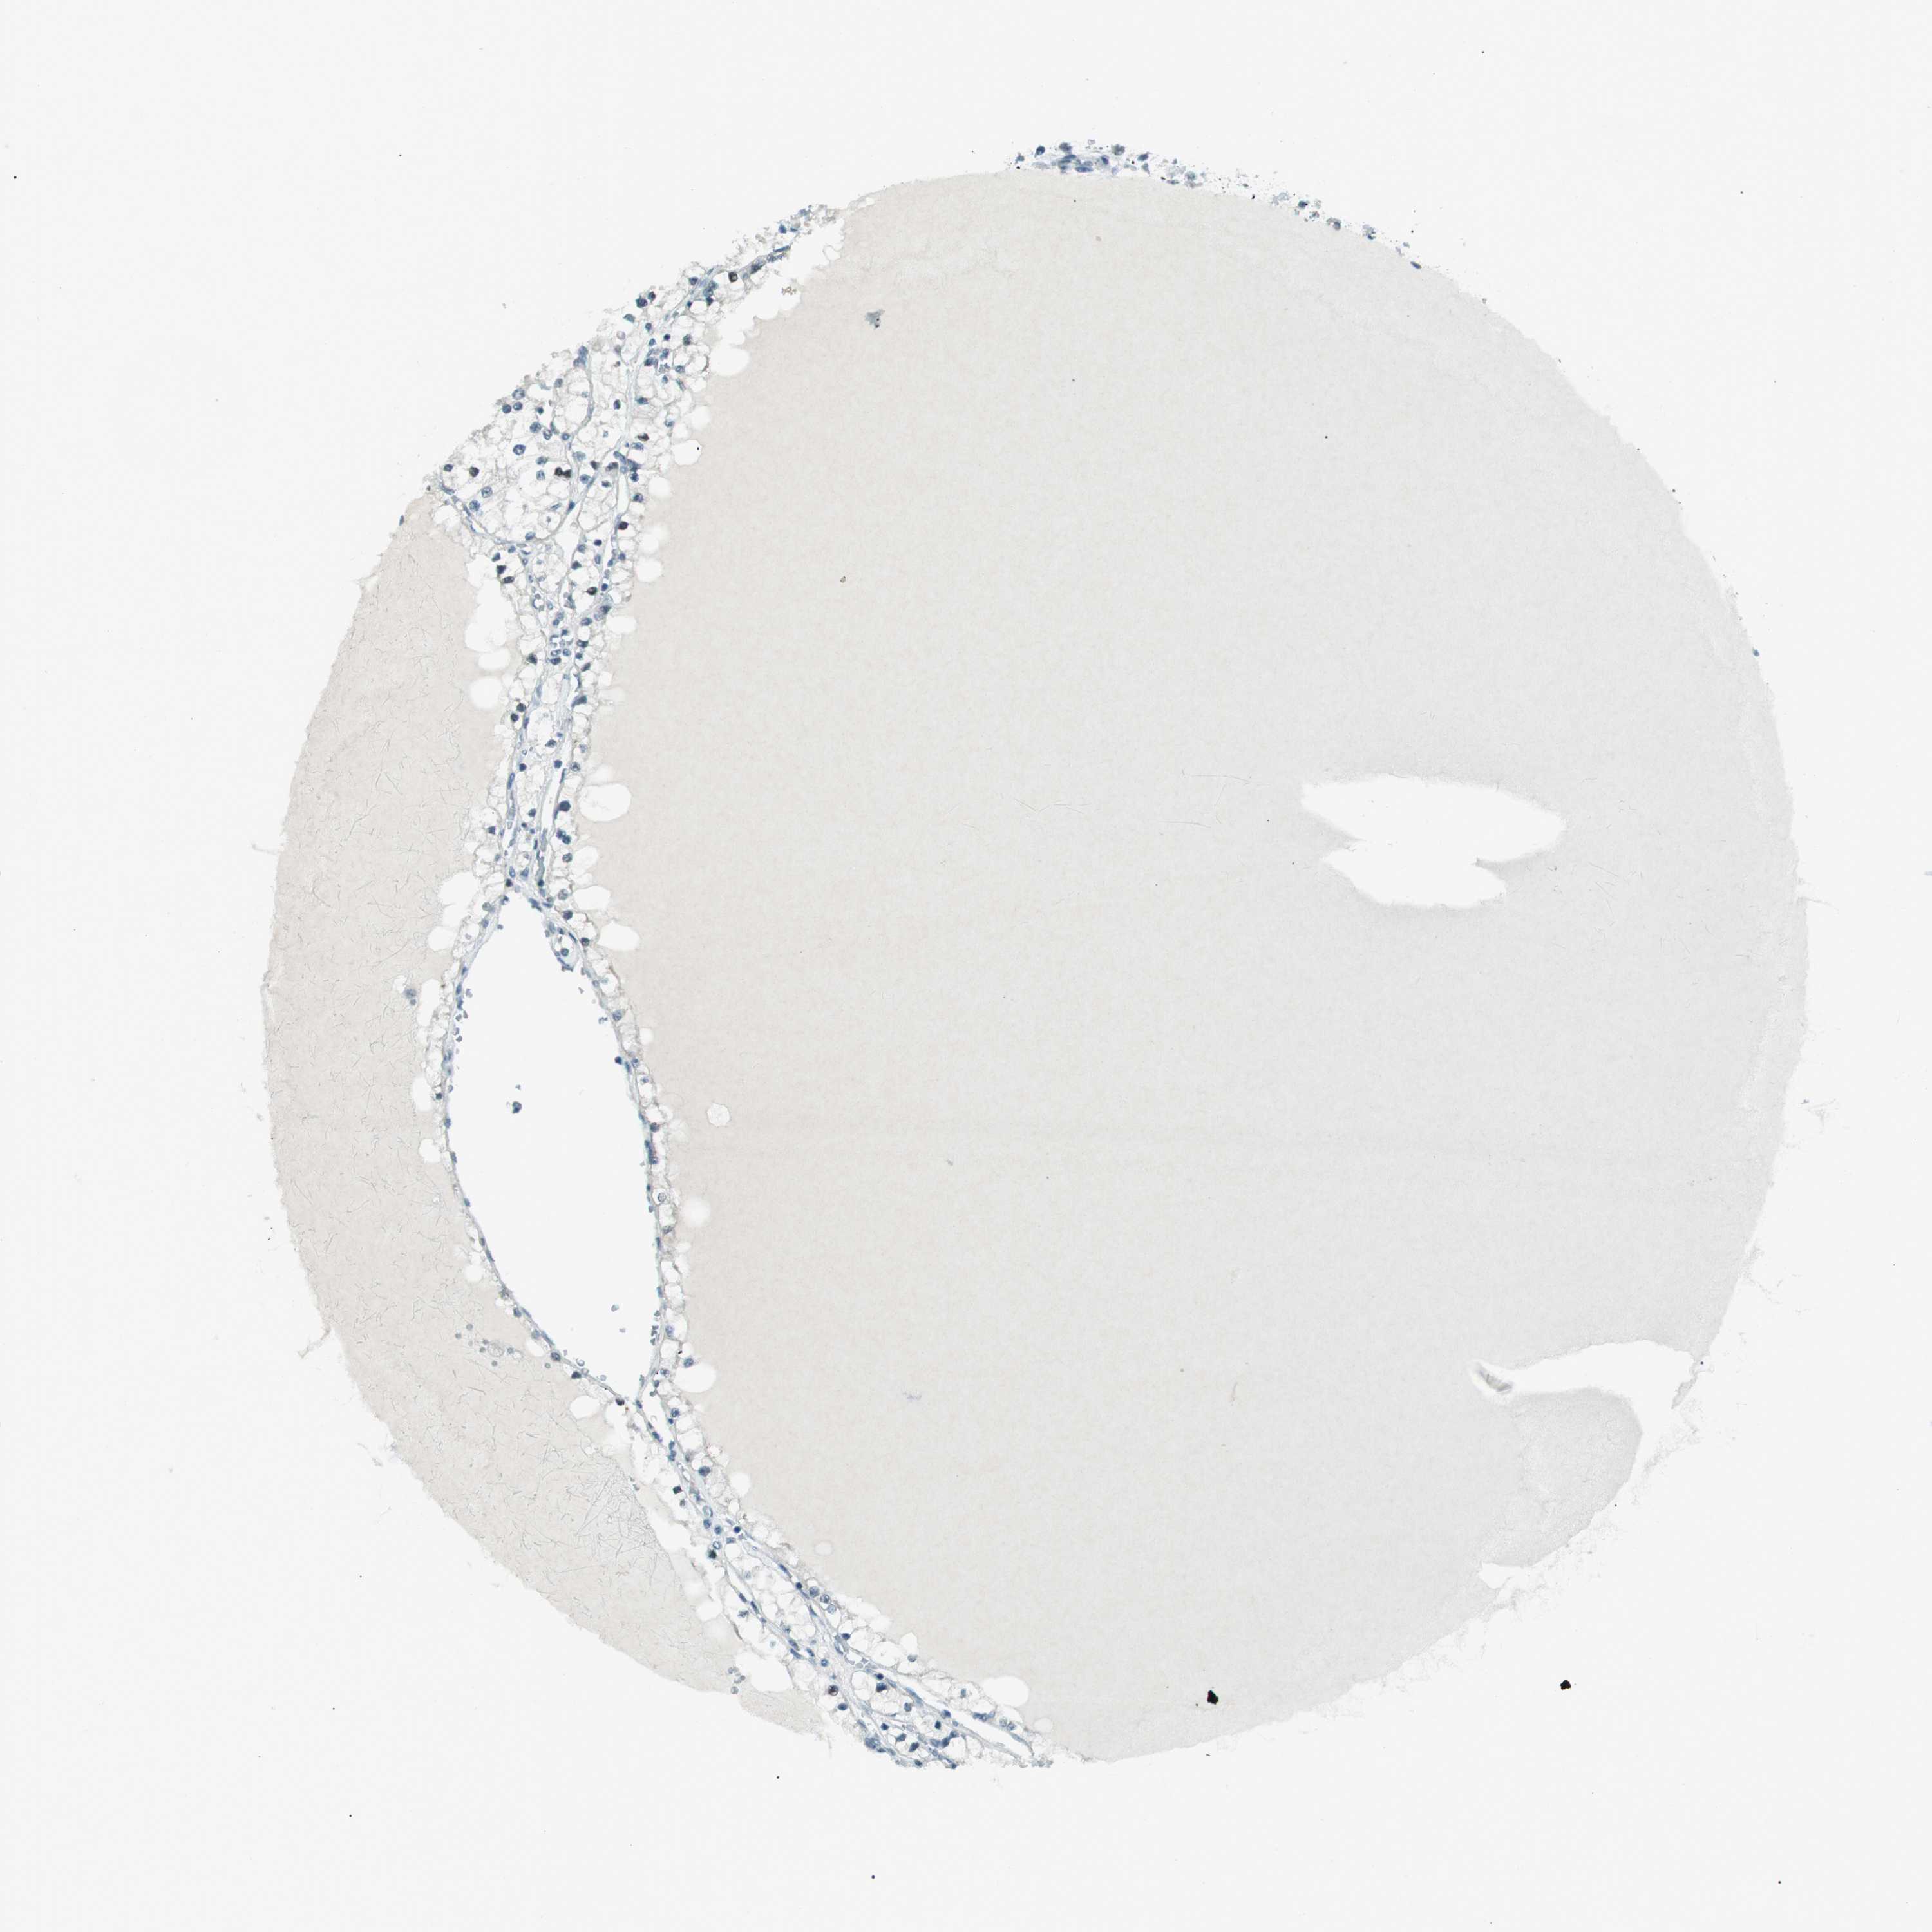

KIDNEY RENAL PAPILLARY CELL CARCINOMA (TCGA) - Interactive survival scatter ploti

The Survival Scatter plot shows the clinical status (i.e. dead or alive) for all individuals in the patient cohort, based on the same data that underlies the corresponding Kaplan-Meier plots. Patients that are alive at last time for follow-up are shown in blue and patients who have died during the study are shown in red.

The x-axis shows the expression levels (FPKM) of the investigated gene in the tumor tissue at the time of diagnosis. The y-axis shows the follow-up time after diagnosis (years). Both axes are complimented with kernel density curves demonstrating the data density over the axes. The top density plot shows the expression levels (FPKM) distribution among dead (red) and alive patients (blue). The right density plot shows the data density of the survived years of dead patients with high and low expression levels respectively, stratified using the cutoff indicated by the vertical dashed line through the Survival Scatter plot. This cutoff is automatically defined based on the FPKM cutoff that minimizes the p-score. The cutoff can be changed by dragging the vertical line or by entering a cutoff value in the square labeled "Current cut-off".

Under the Survival Scatter plot the p-score landscape (black curve; left axis) is shown together with dead median separation (red curve; right axis). Dead median separation is the difference in median mRNA expression between patients who have died with high and low expression, respectively. It is calculated as follows: median FPKM expression of dead patients with high expression - median FPKM expression of dead patients with low expression. This is intended to aid the user in visually exploring custom cutoffs and the associated p-scores and dead median separation.

Individual patient data is displayed and can be filtered by clicking on one or more of the category buttons on the top of the page. Categories describing expression level and patient information include: high, low, alive, dead, female, male and tumor stages. The scale of the x-axis can be toggled between linear and log-scale by clicking on the "x log" button. Mouse-over function shows TCGA ID, patient information and mRNA expression (FPKM) for each patient.

& Survival analysisi

Kaplan-Meier plots summarize results from analysis of correlation between mRNA expression level and patient survival. Patients were divided based on level of expression into one of the two groups "low" (under cut off) or "high" (over cut off). X-axis shows time for survival (years) and y-axis shows the probability of survival, where 1.0 corresponds to 100 percent.

PJA1 is not prognostic in Kidney Renal Papillary Cell Carcinoma (TCGA)